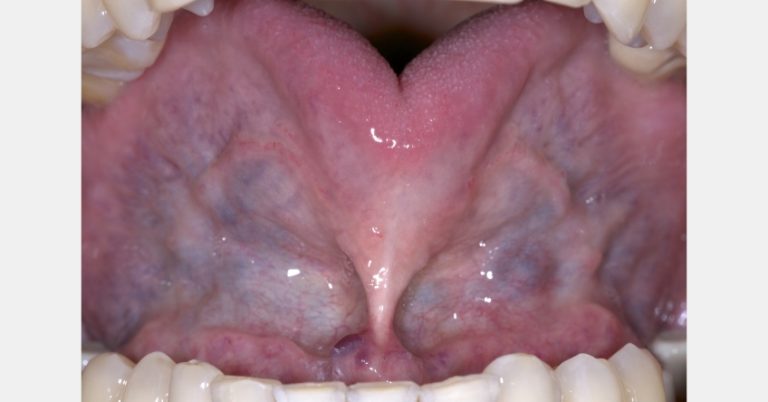

Tongue Tie and Sleep Apnea: The Craniofacial Connection

Dr. Jeffrey Rouse reviews the literature and recent studies on the connection between tongue tie and sleep apnea. Read on…By Jeffrey Rouse

Integrating Myofunctional Therapy Training into Your Dental Practice with BROOM Screening

Conducting myofunctional therapy training for dental staff using the screening tool ‘BROOM’ provides details about your patient’s health. Before your…By Brittny Sciarra

Maxilla Is Key in Comprehensive Treatment Planning

Dr. Jeffrey Rouse builds the case for dentists to keep the maxilla in mind when planning comprehensive treatment.By Jeffrey Rouse

Understanding and Recognizing Mouth Breathing

How can you explain to patients why nasal breathing is healthier than mouth breathing? This article provides research-based info to…By Abigail Pfeiffer